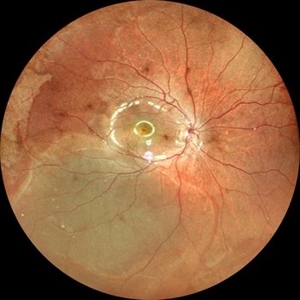

Old Supero-Temporal Branch Retinal Vein Occlusion with Macular Hole Right Eye Fundus

Fundus photograph of a 36-year-old female presented with supero-temporal branch retinal vein occlusion with macular hole in right eye.

Photographer: Dr. Akansha Sharma-Retina Foundation

Condition/keywords: branch retinal vein occlusion (BRVO), macular hole